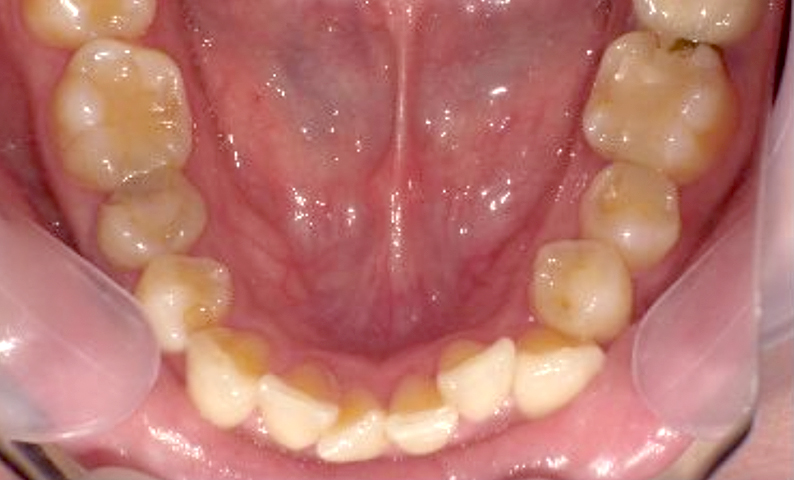

症例_002 下顎だけの部分矯正

治療期間:6ヶ月金額:21万円+税女性前歯のデコボコ下の前歯だけ

| Before | After |

|---|---|

|